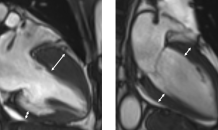

- 6돌연사 키우는 조용한 병…'비후성 심근병증' 아세요?